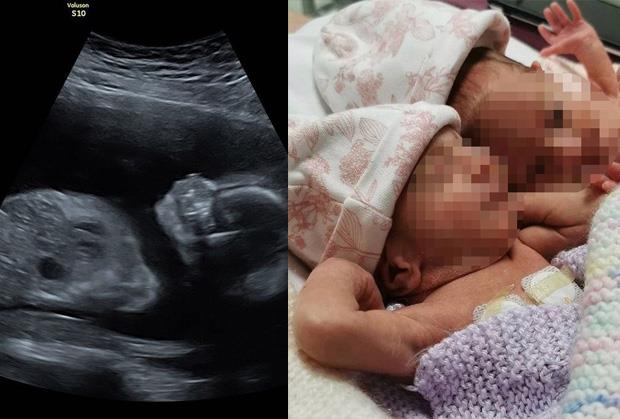

Ceo svet obilazi dirljiva slika dve bliznakinje, rođene pre vremena, koje su na svet došle na poseban način.

Arija i Skajlar Morgan Troden su na svet došle carskim rezom, potpuno zagrljene. Fotografiju je napravila zapanjena babica, koja je prokomentarisala da su i ona i lekar ostali bez teksta kada su ih videli u takvom položaju. Bez reči su ostali i očevi devojčica, Kajran Troden (25) i Rajan Morgan (28) iz Sarija.

Bliznakinje je na svet donela surogat majka, a i na fotografijama sa ultrazvuka vidljivo je da su se i u njenom stomaku devojčice stalno grlile.

NA ULTRAZVUKU SE VIDELO NEŠTO NEOBIČNO! Sve vreme su bile zagrljene, a na porođaju je babica odmah uzela telefon da ih slika! Izvor: Instagram